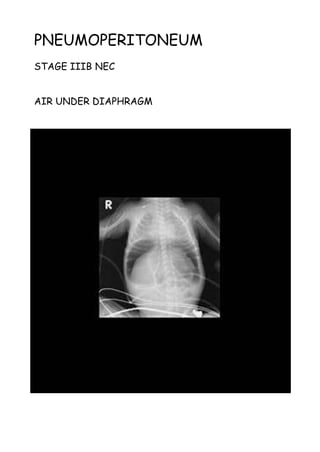

PNEUMOPERITONEUM

STAGE IIIB NEC

AIR UNDER DIAPHRAGM

Adult

The causes of neonatal

pneumoperitoneum are different from

adult pneumoperitoneum and include:

•perforated hollow viscus

• necrotising enterocolitis (NEC):

most common

• meconium ileus in cystic fibrosis

• Hirschsprung disease

• intestinal atresia or web

• peptic ulcer disease

•iatrogenic

• intubation/mechanical ventilation

• rectal thermometer

• enema

Radiographic features

Although these are essentially the

same as in adults, erect chest X-rays

are not obtained, and thus the

diagnosis should be made with supine

films. Additional horizontal cross

table shoot through films or left

decubitus shoot though films may be

performed.

Signs

•football sign

•Rigler's sign